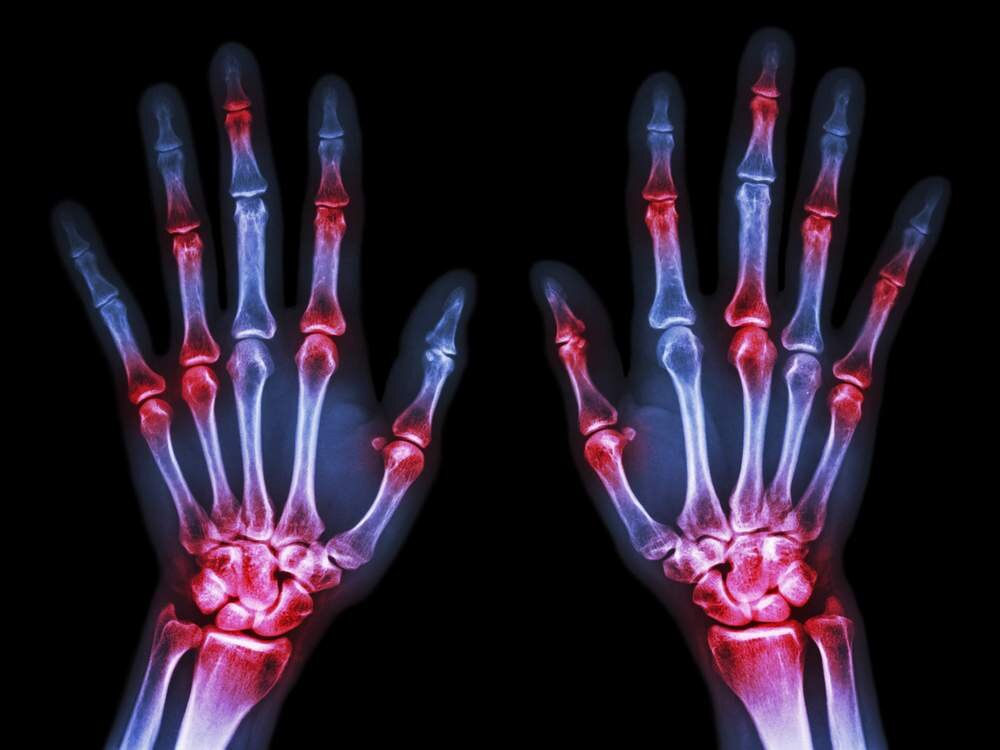

Детский АРТРИТ

Рассмотрим наиболее часто встречающиеся виды артрита:

Ювенильный ревматоидный артрит (ЮРА) хроническое воспаление суставов неясного происхождения. Могут воспаляться как один сустав, так и несколько. Возможно присоединение воспаления внутренних органов сердца, легких, глаз. Требует долгого лечения под наблюдением врача ревматолога.

Ювенильный псориатический артрит может проявиться до появления псориатических бляшек. В первую очередь поражаются мелкие суставы на руках и ногах. Протекает относительно спокойно. У 40% заболевших отмечается деформация суставов. Такой диагноз стоит сейчас у нас. Проявления псориаза и бляшек у дочки нет.